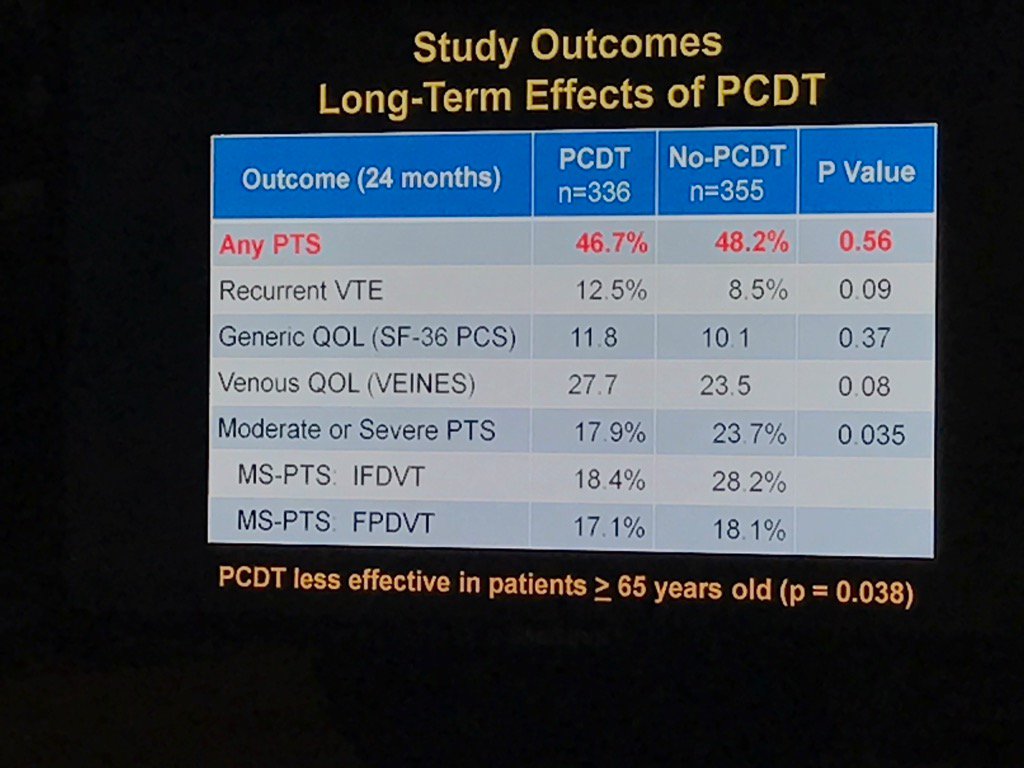

Long term outcomes of ATTRACT are disappointing for the lytic group Society of Interventional Radiology Ido Weinberg, MD